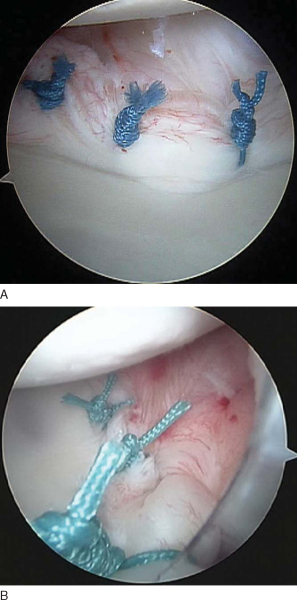

The knot pusher is again passed down one limb to ensure that the tails are not twisted around one another. An arthroscopic knot is now tied to secure the capsulolabral tissue back to the glenoid (

Fig. 3-15

). Many arthroscopic knots have been described; however, the surgeon should become proficient with one sliding-locking knot so it can be tied quickly and reproducibly with little effort. We prefer to use a modified Roeder knot that allows a strong suture buttress. This is backed up with three half-hitches to secure the knot. To reduce the tension on the tissue during tying, an atraumatic tissue grasper can be passed through the anterosuperior portal to translate the tissue while this first knot is tied. The tails of the completed knot are cut with the arthroscopic scissors passed through either the anterosuperior portal or the anteroinferior portal, depending on the optimal angle. This entire process is repeated two or three times to restore the tissue back to the glenoid. The knots should be secure and induce a dimpling effect on the capsulolabral tissue (

Fig. 3-16

).